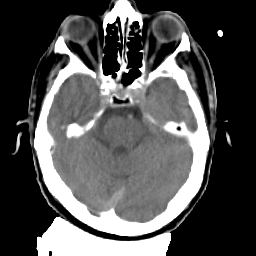

Meningioma: Roentgen-ray CT #2 -- Slice #6

[Home][Help][Clinical] Slice 6